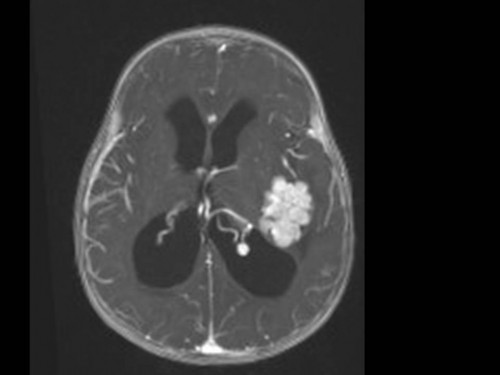

10 Monate altes Mädchen. Der Kinderarzt stellt fest, dass das kleine Mädchen einen recht großen Kopfumfang hat, nicht mit den Augen fixiert und anscheinend auch nicht richtig sehen kann. Damit bestätigt er die größten Befürchtungen der Eltern, denen in den letzten Wochen aufgefallen war, dass ihre Tochter nach keinem Spielzeug mehr greift und sie nur dann anlächelt, wenn sie zu ihr sprechen.

Bildgebung - MRT